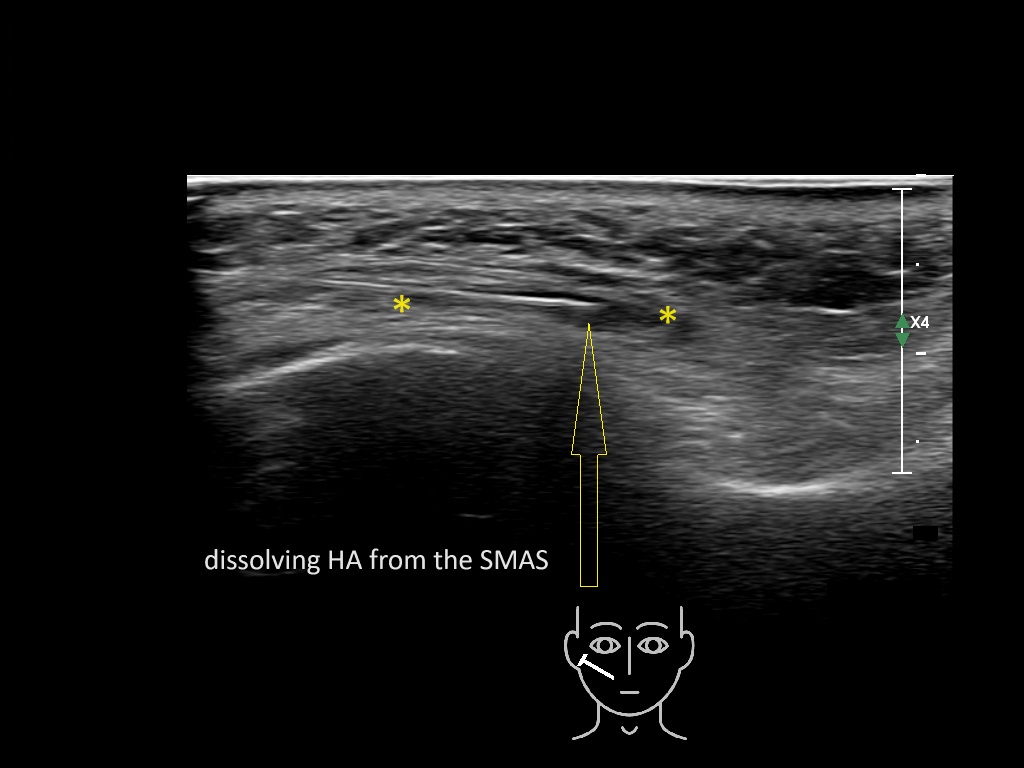

The zygomatic major muscle is embedded inside the midfacial SMAS. Having filler material inside the fibrous layers may result in the limited ability of the muscle to pull the modiolus and thus the oral commissure vertical and horizontal toward the zygomatic arch; this seems to lead in the patient’s perception of an unnatural smile.

Study the first image to recognize the different layers. If you are sure about the layers, swipe to the second image to view the answer (if applicable).